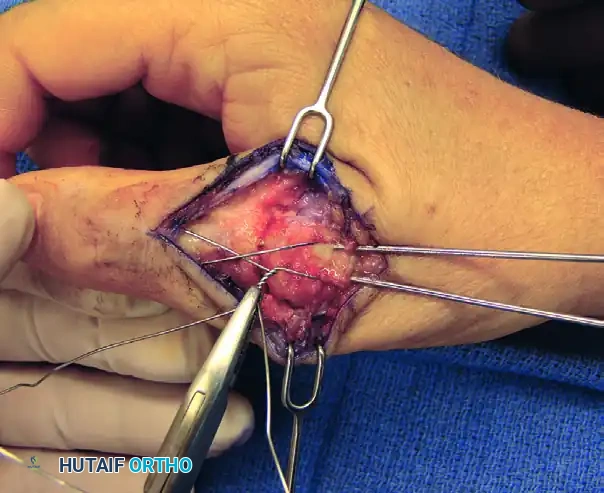

6. Tension Band Application and Compression

The application of the tension band wire is the critical step for achieving dynamic compression.

- Cross the two ends of the stainless steel wire over the dorsal aspect of the joint in a figure-of-eight pattern.

- Pass the wire ends around the protruding proximal ends of the longitudinal K-wires.

- Using heavy needle drivers or wire twisters, twist the wire ends together.

- Surgical Technique: Pull the wire radially outward while twisting to ensure the tension is distributed evenly and the wire tightens down firmly against the bone, compressing the arthrodesis site.

FIGURE 73-40F: Wire twisted and ends buried about the fusion site to achieve dynamic compression.

7. Construct Finalization and Hardware Burial

To prevent postoperative soft tissue irritation, the hardware must be meticulously buried.

- Cut the twisted wire leaving approximately 3 to 4 twists (about 5 mm).

- Bend the twisted knot and tamp it down flat against the dorsal cortex of the metacarpal.

- Cut the proximal ends of the longitudinal K-wires, leaving just enough length to hold the tension band wire. Bend these ends 180 degrees and tamp them into the metacarpal bone. This creates a smooth, low-profile construct that will not impinge on the extensor tendons.

FIGURE 73-40G: Ends of wires cut and tamped into the metacarpal over the low-profile construct.